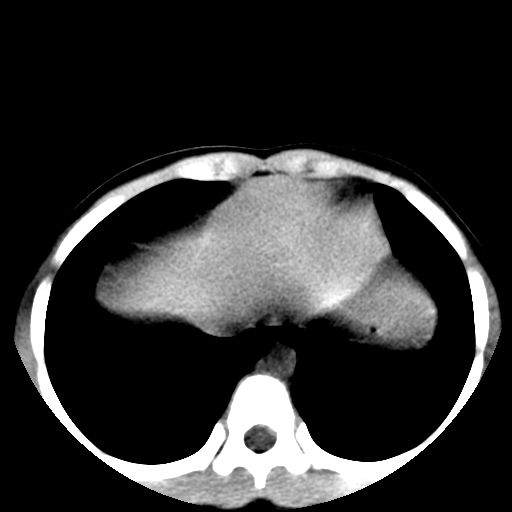

胸部明显是成年女性,定位象上双侧补过牙齿。轴位像上双侧乳腺退化。可以认定胸部与腹部不是一个人。

可以认定胸部与腹部不是一个人。

腹部好象未见异常。

腹部ct平扫未见明确异常

腹部ct平扫不能提示哪里有病变。